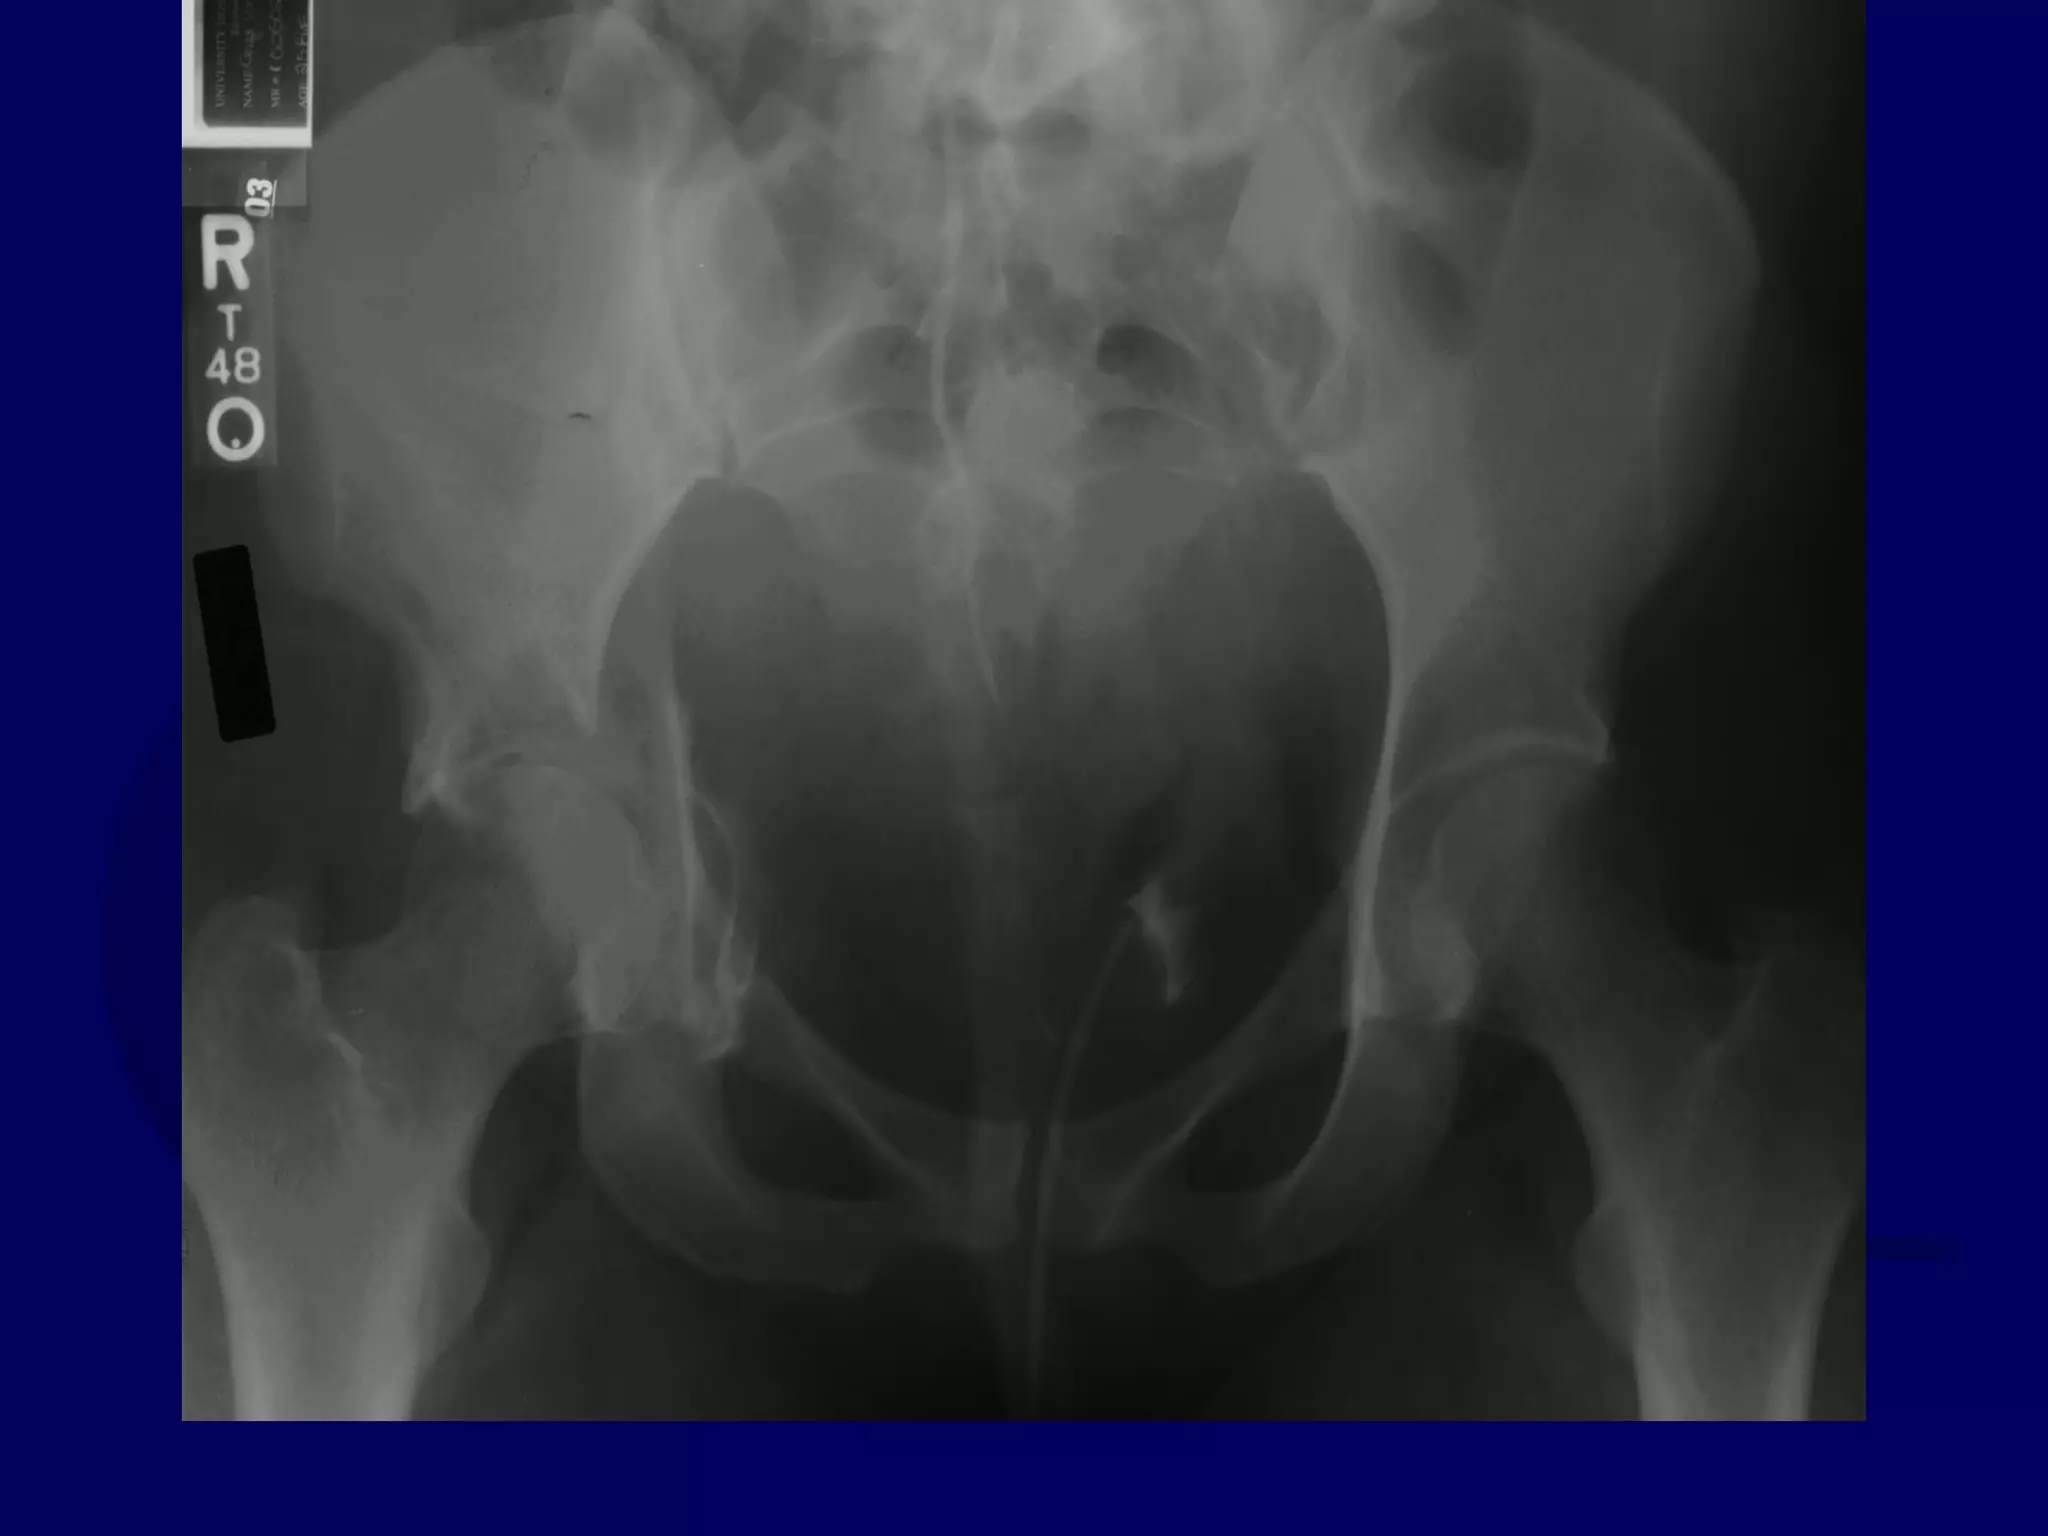

Both Column

Acetabular Fracture

18 Y.O. Female

Isolated Injury

R.C. 00.03.09

SPUR

SIGN